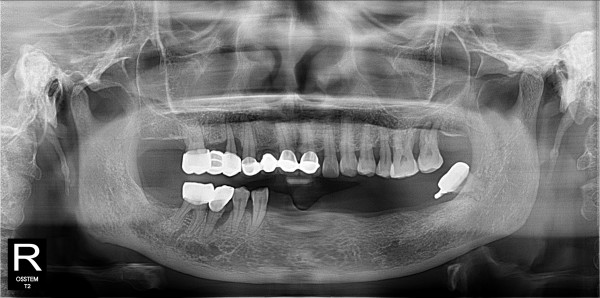

하악 틀니에서 네이게이션 임플란트